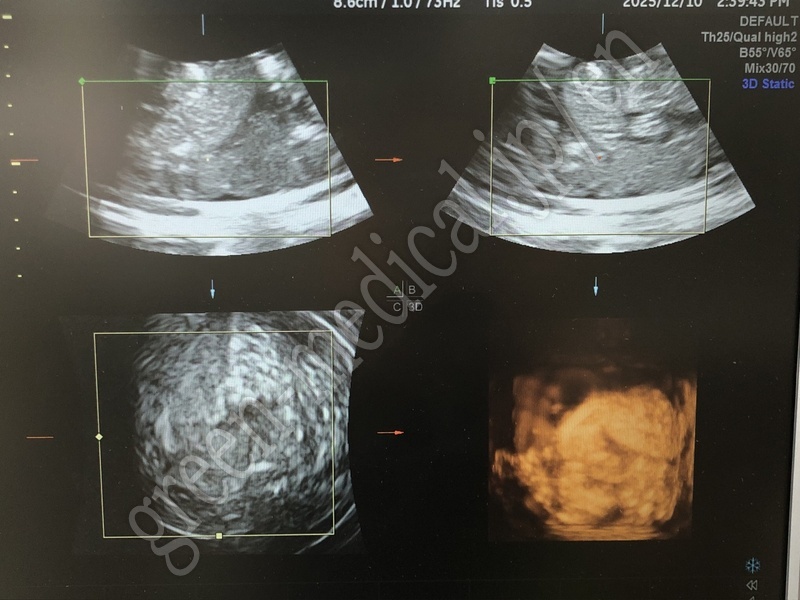

Diagnostic Ultrasound System VOLUSON S6

GE Healthcare

VOLUSON S6